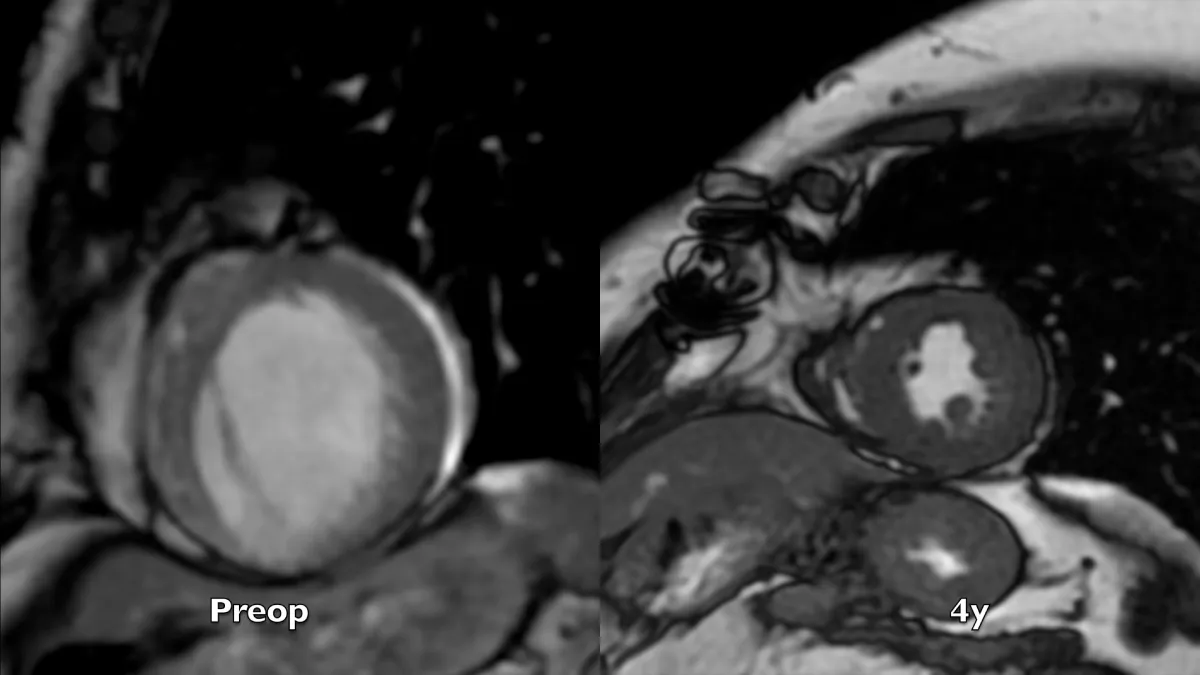

Figure 1: 2D speckle tracking echocardiography 4-chamber systolic frames at three controls, preoperative, 6 days and 4 years after the operation. Note the substantial volume reduction immediately after the operation and the progressive remodeling during time of volume and chamber geometry.

Video 1: Echocardiography apical four-chamber view; comparison between preoperative, 6 days, and 4 years after the operation controls. Note the substantial volume reduction immediately after the operation an d the progressive, positive adjustment during time of volume and chamber geometry, promoted by structural and geometric physiological reconstruction.

Preoperative imaging shows a very large dyskinetic region equal to around half of the ventricular chamber, conditioning a box-shaped ventricle with severely impaired global contraction, wall thickening, and diastolic function. Surgical reconstruction achieved an elliptic chamber with a normal volume and a new apex that were maintained along the years, gradually improving global ejection fraction and diastolic indices (Table 1), showing a positive remodeling induced by the optimised geometrical and functional parameters, left ventricular torsion included. Remote regions show a renewed, increased thickening granted by the better chamber geometry and fibers’ realignment, and the whole left ventricle shows a time-dependent restoration of its functional reserve, preoperatively hidden by the unfavourable functional conditions.